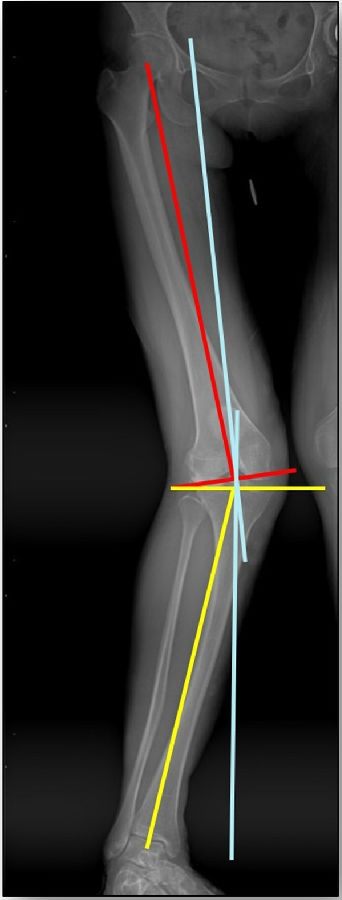

患者二,女性,膝外翻,膝外侧疼痛。通过做畸形分析后发现,该患者同时存在股骨侧畸形、胫骨侧畸形和关节内畸形(LDFA=82°,MPTA=104°,JLCA=6°)。

对于这类病人如何进行术前设计的关键点就在于目标力线应如何设计。要在骨性截骨的时候纠正骨性畸形,关节内畸形要通过关节内的方法解决。因为JLCA不平行,所以要同时画股骨侧关节线和胫骨侧关节线,并垂直于股骨侧关节线做出股骨侧目标力线,垂直于胫骨侧关节线做出胫骨侧目标力线。

根据各自目标力线,分别计算股骨内侧闭合和胫骨内侧闭合角度。

此患者股骨内侧闭合6°,经股内侧闭合13°。